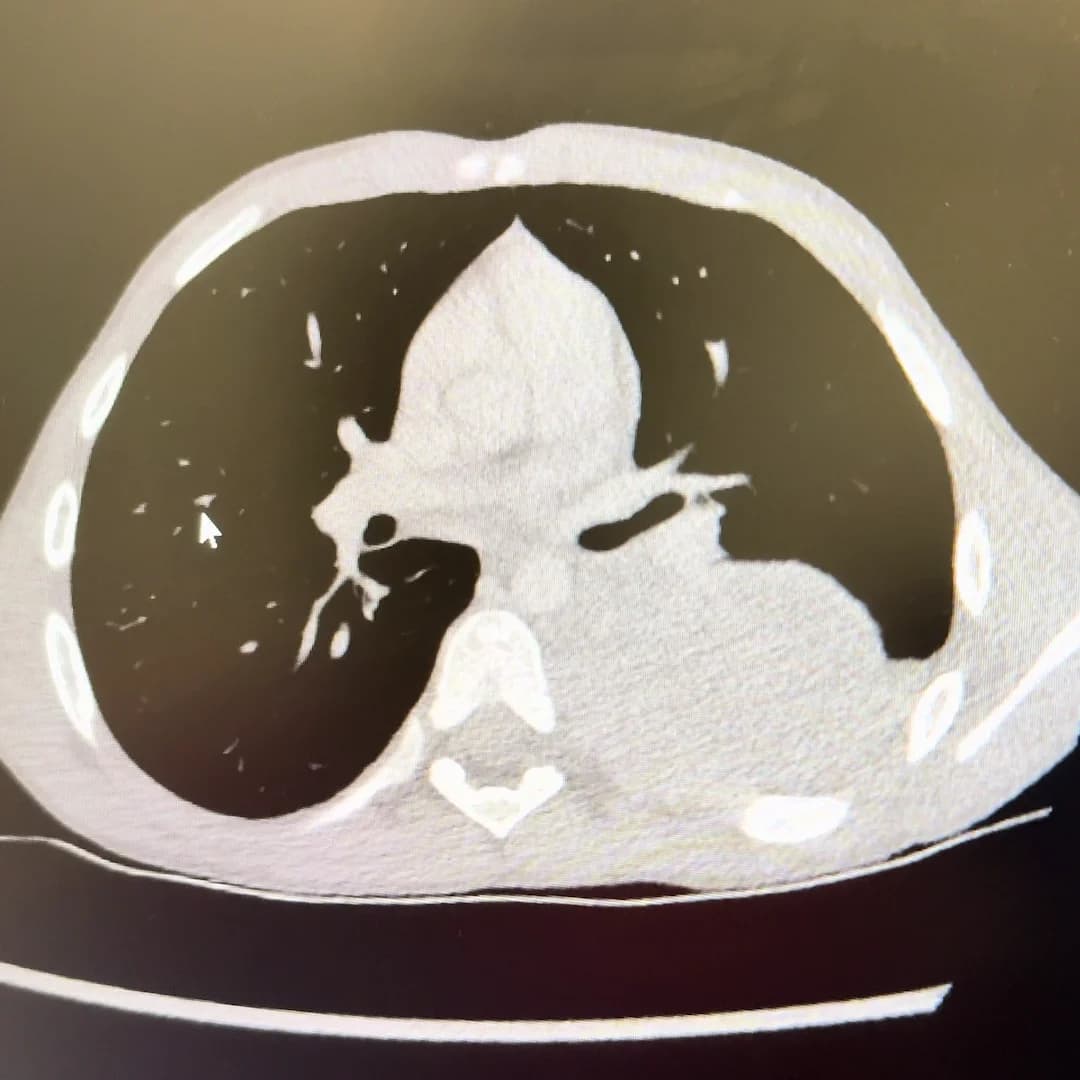

CT scan revealing the tumour mass behind Aleks's lung.

The weeks that followed were a whirlwind of appointments, hospital visits, and silent hopes. Aleks remained completely asymptomatic. Even some doctors looked at him with disbelief — he seemed entirely healthy. Despite that, Aleks went through everything: CT and MRI scans, blood tests, urine tests, full skeletal surveys, a bone marrow biopsy, and a surgical biopsy of the tumour itself. At times, he had more tests in a week than most adults have in a year. And yet, through it all, he never complained or stopped smiling.

In Aleks' case, the tumour was localised, nestled behind his lung and in front of his spinal cord—close to the heart and major blood vessels but without attacking any vital organ, just silently growing in one of the 'empty' spaces within the body. But it had not spread. There was no sign of it in his bones, lungs, or marrow. And despite its size (almost the size of my wrist), it had caused no symptoms whatsoever.